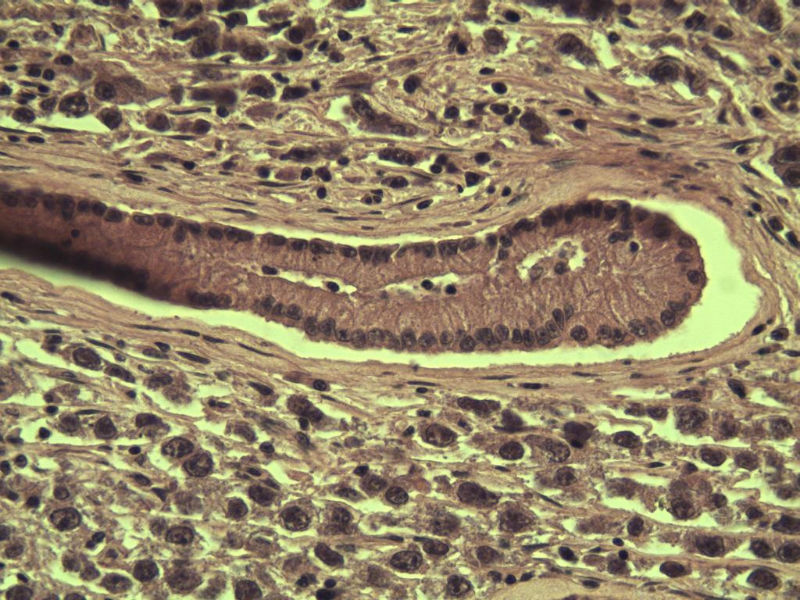

腹腔隐睾图4

名称:图4

描述:a214.Jpg.jpg